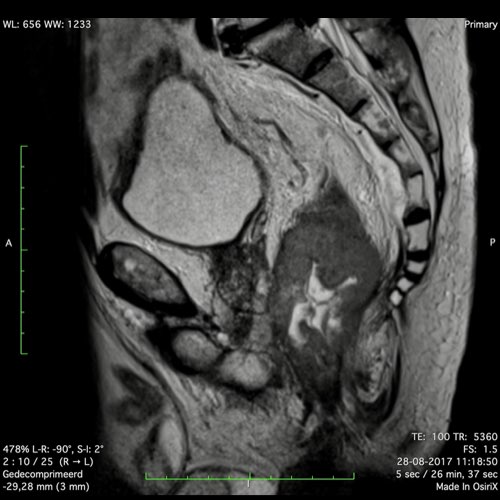

Hình ảnh

Các hình ảnh được cung cấp cho thấy ung thư biểu mô tế bào nhẫn với tình trạng dày lan tỏa thành trực tràng, hình ảnh bia bắn điển hình, và sự xâm lấn mỡ mạc treo trực tràng.